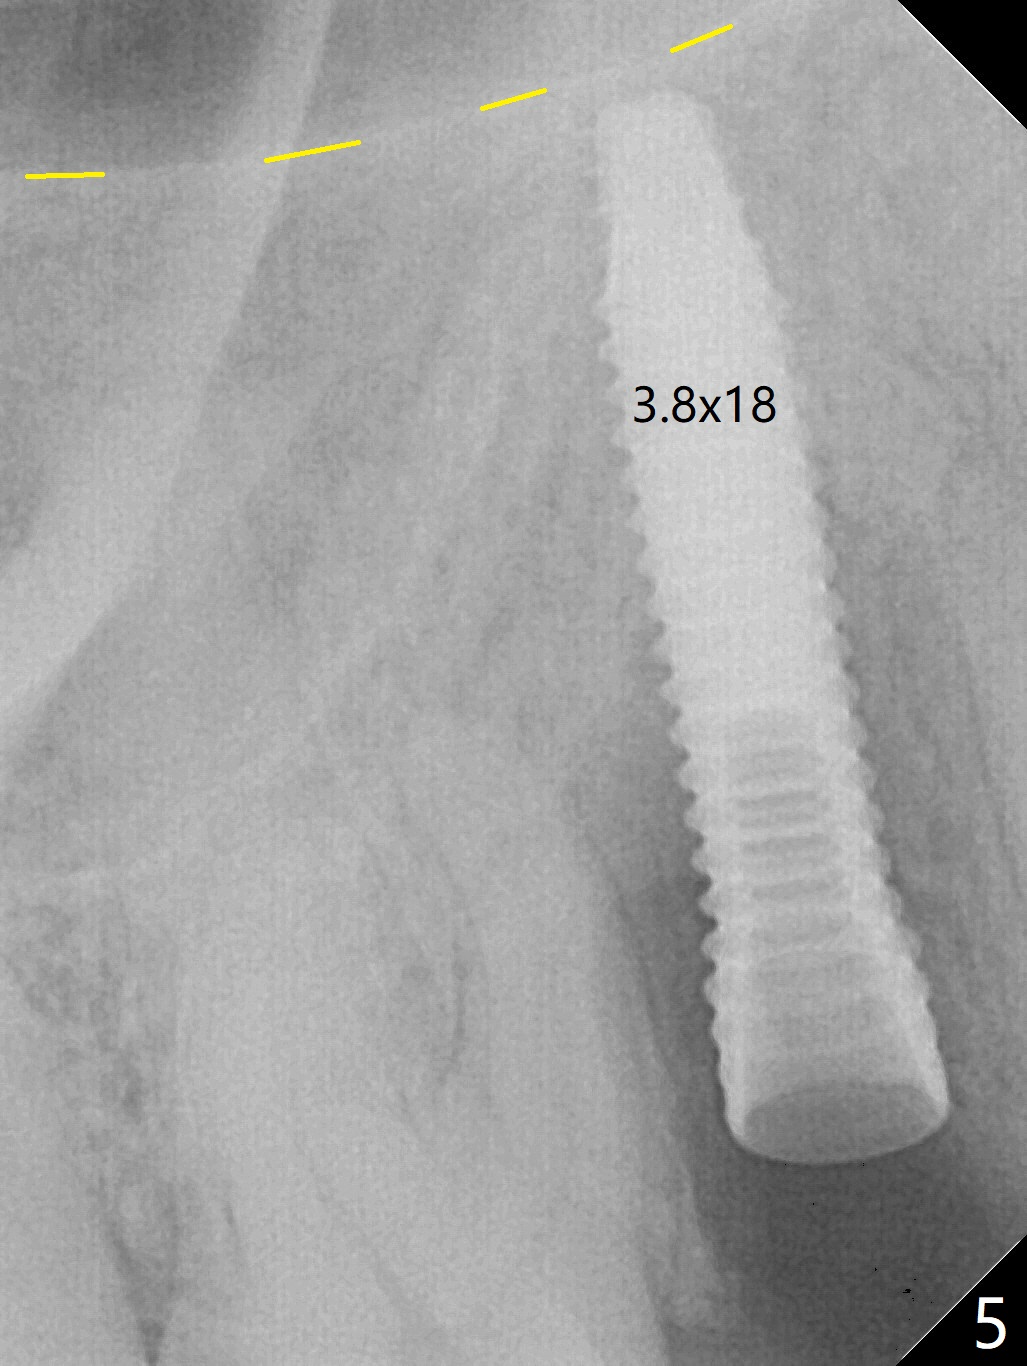

When the tooth #4 with vertical root fracture (Fig.1) is extracted, the buccal plate is found to be lost. The lowest point of the defect is shown as black dashed line in Fig.2 (yellow dashed line: sinus floor). After use of 2.5 mm reamer for 21 mm (buccal gingival level) and 3.0 mm reamer for ~17 mm, a 3.8x15 mm dummy implant is placed with 30 Ncm and 1.85 mm apical space (Fig.3 pink outline). A 3.8x18 mm (definitive) implant is placed with <40 Ncm with the implant plateau apical to the lingual crest (Fig.4,5). The buccal plate defect is repaired by Vanilla Graft (Fig.6 *) before and after insertion of a 4.5x4(3) mm abutment. The buccal plate defect seems to being repaired 4 months postop (Fig.7). Occlusal wear suggests bruxism, which is also associated with the root fracture. Night guard is recommended. The defect repair is close to completion 8 months post cementation (Fig.8). The crown/abutment is found to be loose 1 year 4 months post cementation and retightened without checking whether there is clinical 2nd DO caries of #3 (Fig.9, "sensitive to water pik"). A few days later, DO composite is being removed. It is difficult to determine whether the 2nd DO caries or gap has been removed with the neighboring crown in place. When the crown/abutment is removed and gingival retractions are inserted, there is no decay. The gap is removed. With Toflemire in place, the crown/abutment is reseated and hand tightened; after packable composite, the crown/abutment is removed, there is no more DO gap.